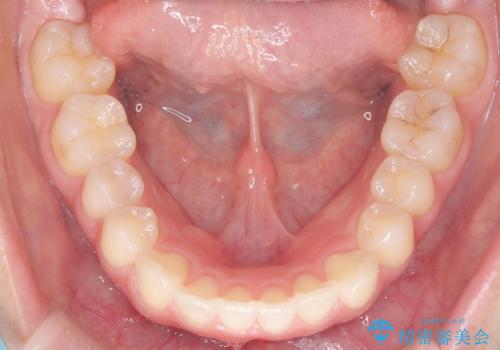

下顎前歯の叢生を短期間で改善

- 患者様は、下顎前歯のガタガタ(叢生)の改善を希望して来院されました。診断の結果、非抜歯で治療可能であると判断し、透明で目立たないインビザラインを使用する矯正治療計画を立案しました。短期間での治療を希望されていたため、IPR(歯間削合)を併用してスペースを確保しながら、効率的に歯を並べることを目指しました。

治療では、インビザラインを用いて計画的に歯を移動させ、短期間での歯列改善を実現しました。IPRを行うことで、抜歯をせずに必要なスペースを確保し、歯列全体を整えました。治療中は、装置の適切な装着時間を守ることが重要であり、患者様にも継続的な協力をお願いしました。また、歯肉や歯根への負担を最小限に抑えるため、歯の移動を慎重に管理しました。結果として、短期間で下顎前歯の叢生を改善し、自然な見た目と機能性を兼ね備えた歯列を実現できました。